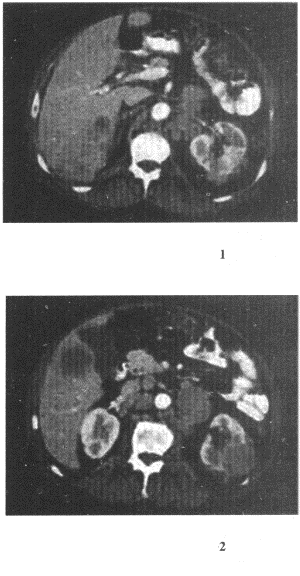

患者,男,54歲,左側腰痛,伴間歇性血尿2個月余,體格檢查左腎區叩擊痛,CT增強掃描如圖所示。

12.結合圖像所示,下列哪項描述正確

正確答案:12.E;13.C;14.D;15.D;16.A